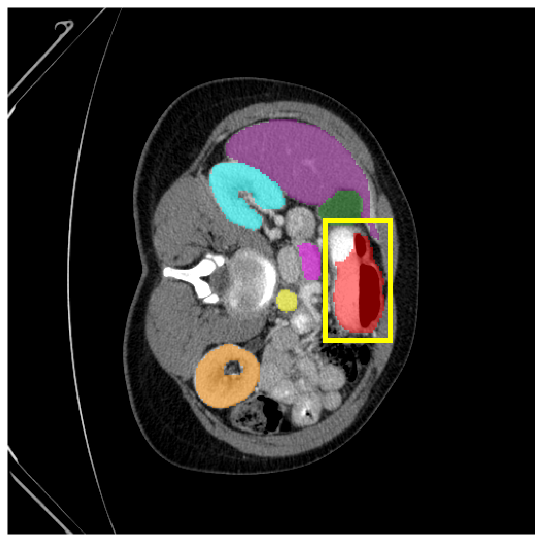

4.3.2 Visual Comparisons

Visualization of our method on the Synapse and ACDC datasets is shown in Fig. 3(a) and Fig. 3(b). For the Synapse dataset illustrated in Fig. 3(a), FCT failed to accurately segment SM and GB, while MERIT achieved precise segmentation of SM but struggled with GB. In contrast, our method achieved accurate segmentation of both SM and GB. Regarding the ACDC dataset shown in Fig. 3(b), while previous methods achieve comparable segmentation of the Myo and LV to the GT, they exhibit noticeable errors on the RV, including invasion into adjacent organs and misrecognition. On the other hand, our method accurately segments across all three structures Myo, LV, and RV, performing as precisely as the GT. We demonstrate the superiority of our method quantitatively and qualitatively.

To demonstrate the superiority of our method, additional qualitative comparison results for the ACDC and Synapse datasets are presented in Fig. 6, Fig. 7, respectively. Notably, in the case of GB, the quantitative results in Fig. 7 show relatively lower performance in ‘only ’. However, the visualization results in Fig. 7 reveal instances where the enhanced images identified GB regions that the original images failed to segment, albeit with some boundary over-segmentation. In such scenarios, our proposed method successfully leveraged the information from enhanced images to achieve more accurate GB segmentation. Note that this finding underscores the fact that even when quantitative performance metrics appear lower, the additional information provided by enhanced images can be valuable in the actual segmentation process.